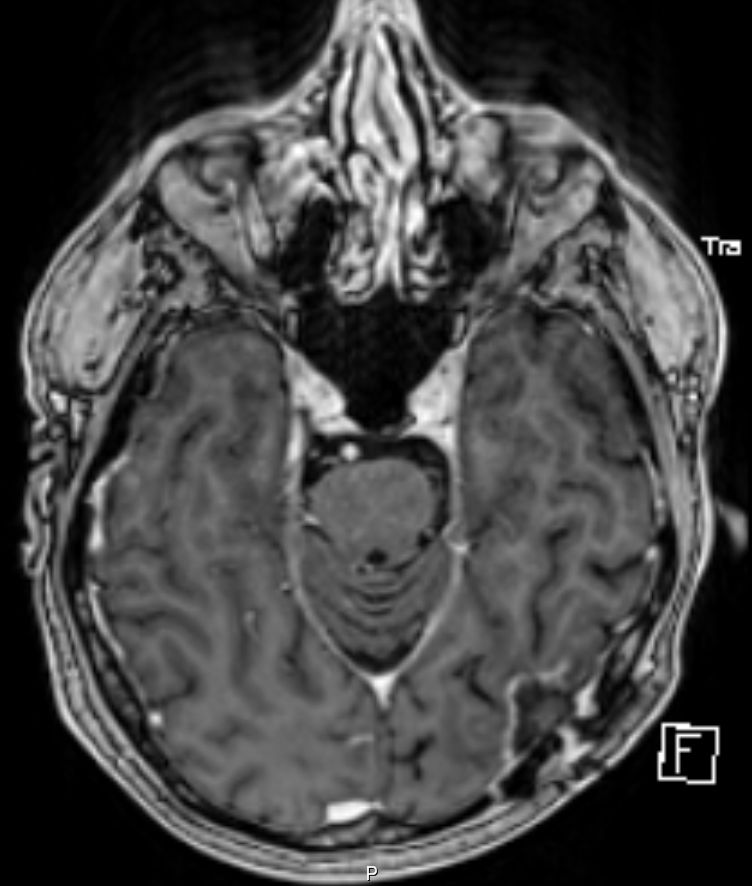

• 54-jähriger Mann, der vor 4 Jahren ein Adenokarzinom des rechten Lungenoberlappens cT4 cN1 M0 entwickelte

•  Cisplatin / Alimta - Chemotherapie, dann Radio –Chemotherapie 50Gy, 3 Zyklen simultan Cisplatin und Pemetrexed

• extrapleurale Oberlappenresektion,  Lymphadenektomie

• postoperatives Stadium ypT3 ypN0 L0 V0 G3

• adjuvante Bestrahlung der Thoraxwand rechts ED 3 Gy, GD 30 Gy

• vor 2 Jahren Metastase links parieto – occipital,  neurochirurgische Entfernung, Bestrahlung des Neurokraniums mit 30 Gy, ED 3 Gy

• vor 1 Jahr  Exstirpation einer Hirnmetaste links occipital, Bestrahlung des Hirnmetastasenbettes links occipital mit 40 Gy, ED 2 Gy

Die linke Spalte zeigt MRTs vor 7 Monaten, die rechte Spalte aktuelle MRTs.

Die MRTs zeigen eine Zunahme der Gadolinium-anreichernden Bezirke. Die Exzision erbrachte Großhirngewebe mit Anteilen einer Nekrose. Kein Tumorgewebe.